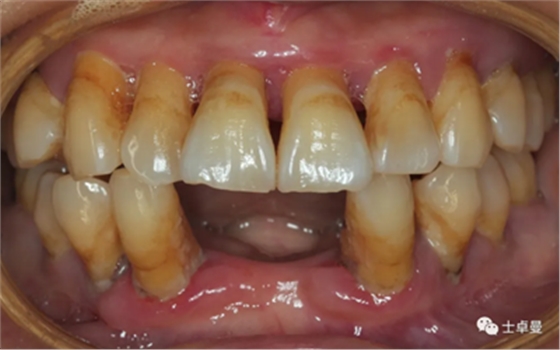

口內(nèi)檢查

臨床檢查:17、37、32-42、37缺失;

前牙區(qū)牙齒扇形移位,口腔衛(wèi)生狀況較差;

菌斑指數(shù):2;

牙石指數(shù):3,色素 (+);

牙齦顏色暗紅,腫脹,質(zhì)地松軟;

口內(nèi)余留牙松動度II°~III°;

根分叉病變III°~IV°。